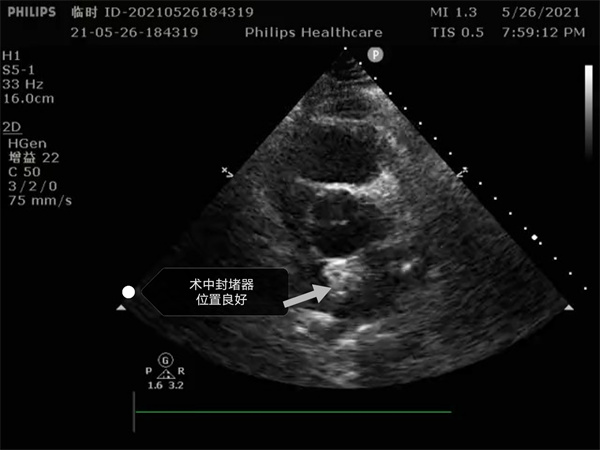

尤其是患者是個三房心,正常的人是有二個心房,這是一種少見的先天性心臟畸形, 如何在三房心把這個洞堵住,而且不影響心臟正常結(jié)構(gòu),是這個手術(shù)難點。沈主任組織全科進(jìn)行術(shù)前討論,5月26日下午5點開始手術(shù),導(dǎo)絲如何在不規(guī)則的只有米粒大小的卵圓孔里通過,鞘管如何通過,如何進(jìn)入卵圓孔連接的副房,避免封堵器夾住隔膜,這些難點在術(shù)中被沈主任團(tuán)隊一一化解,手術(shù)歷時二小時,隨著封堵器成功釋放,導(dǎo)管室外響起來熱烈的掌聲。

就這樣三房心合并卵圓孔未閉發(fā)生過三次腦梗的患者,在安康市中心醫(yī)院心內(nèi)科導(dǎo)管室成功進(jìn)行了國內(nèi)第二例介入封堵手術(shù)。